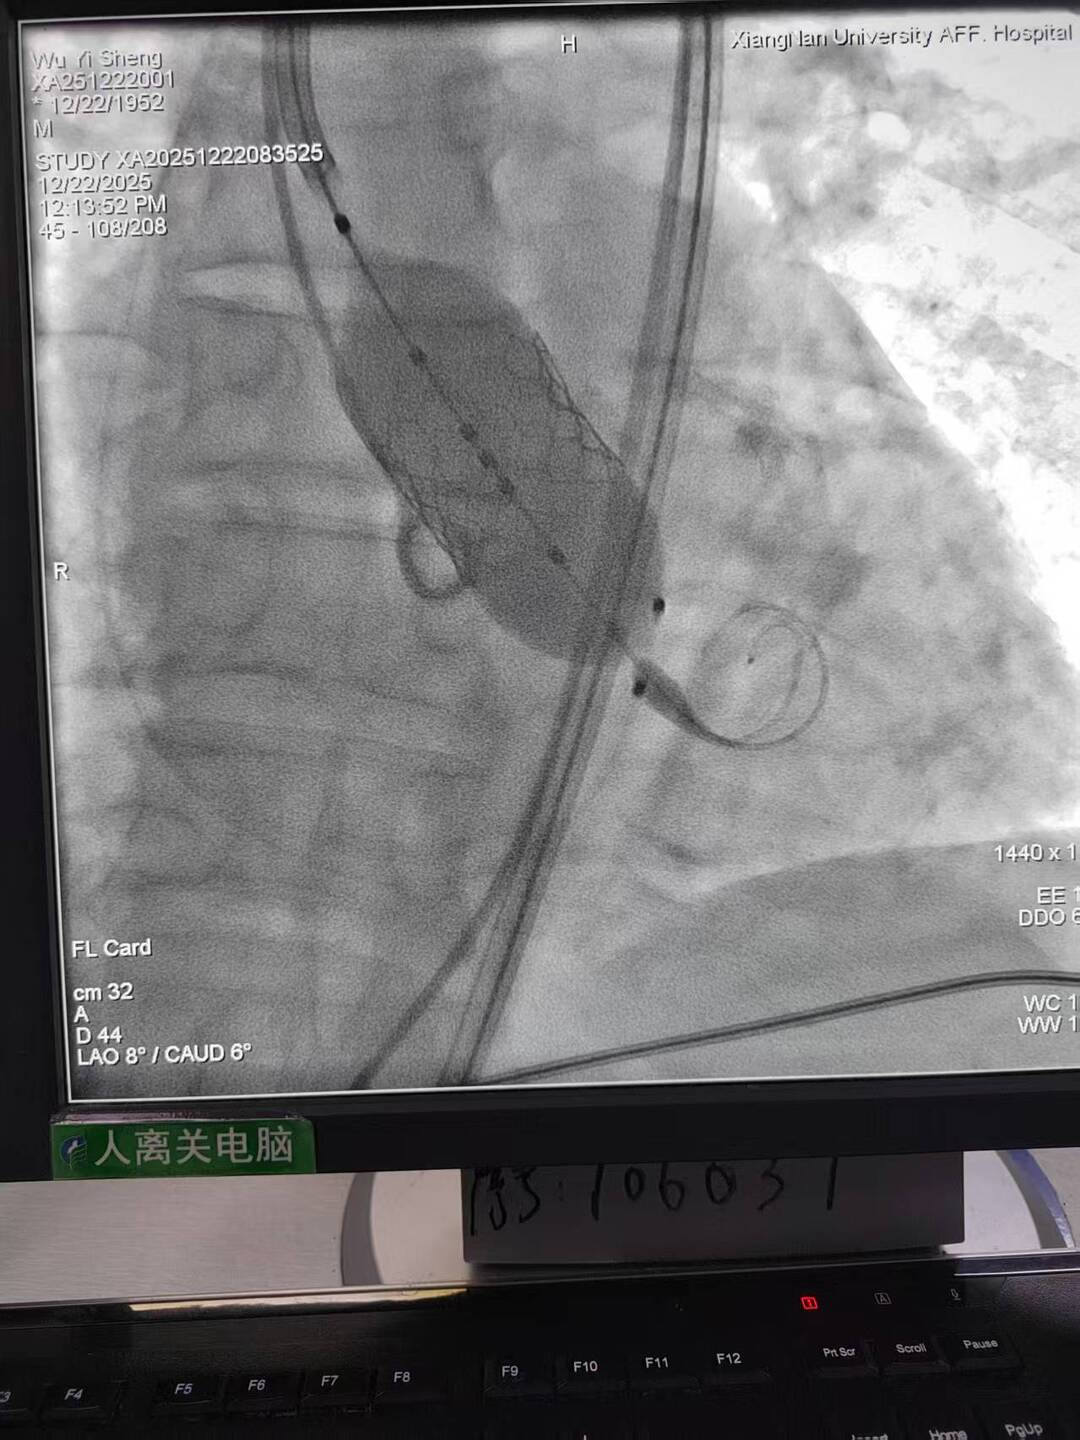

手术过程犹如在心脏内进行的“微雕”和“换门”工程,步骤环环相扣,每一步都考验着术者的技术功底与团队协作默契。术中,团队首先利用先进的可扩张血管鞘,在严重钙化狭窄的右侧股动脉腔内成功建立安全的手术通路;随后经该微创入路,先通过球囊扩张术为冠状动脉植入支架,快速恢复心肌血供;紧接着,在同一手术台、同一入路下,精准将人工主动脉瓣输送至病变位置并成功释放,顺利替换失灵的原生瓣膜。整个过程中,团队成功克服了外周血管入路困难的核心挑战,确保手术各环节无缝衔接、精准落地。

术后,患者主动脉瓣功能即刻恢复正常,冠状动脉血流重回通畅,胸闷、气促等不适症状显著缓解。经过后续康复护理,患者已顺利出院,重获正常生活能力。